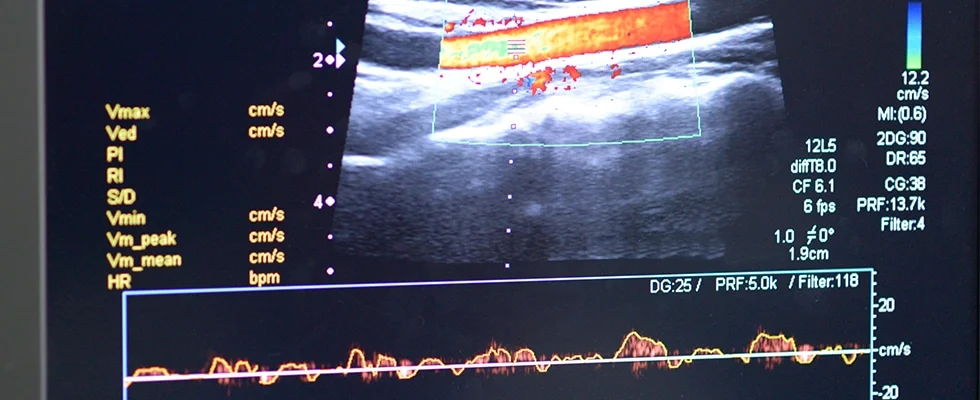

Ultrasound Use for Vascular Access and Basic Cardiac and Pulmonary Assessment for Nurses

Daniel Nash, CRNA, DNAP reviews how nurses can use ultrasound for vascular access and basic cardiac and pulmonary assessments.